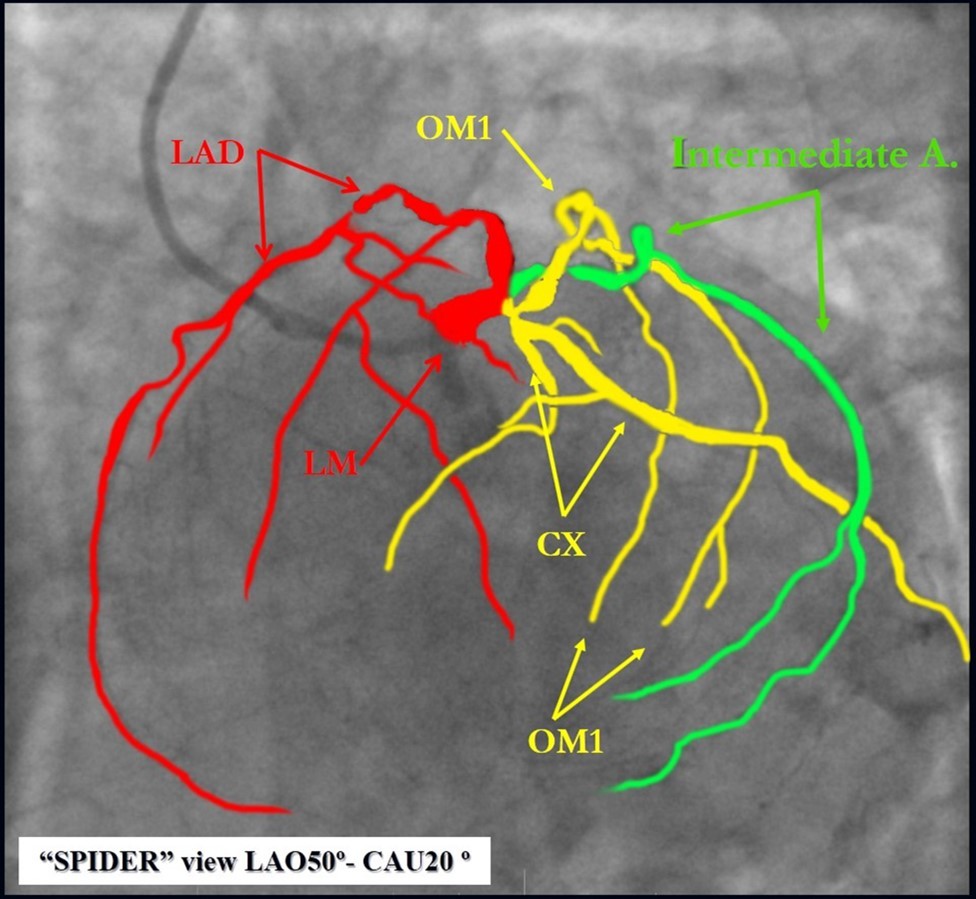

Angiography revealed rare anatomical variation LMCA quadrifurcation (Figure 1, Figure 2), 50% stenosis of the distal part of the LMCA, 40% stenosis of the ostial segment of left anterior descending (LAD) artery and diffuse prolonged 70-75-95% stenosis in mid-segment (Figure 3), 75% stenosis of the ostial segment of the circumflex (CX) artery, 75% stenosis of the ostial segment of the first marginal branch (OM1), 75-90% stenosis of the proximal segment of the intermediate artery (IMA), prolonged diffuse severe 90-95% stenosis of mid-segment of the right coronary artery (RCA) (Figure 4).

Figure 1.Quadrifurcation of the left main coronary artery

Figure 2.Schematic presentation of the left main quadrifurcation.